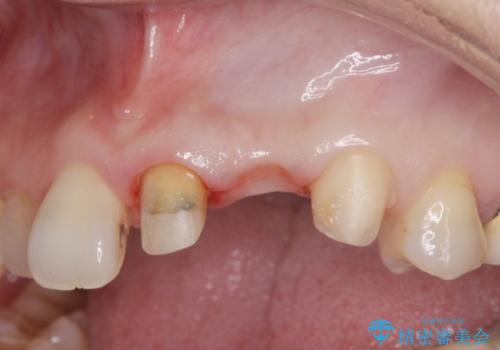

X線撮影や歯周組織検査から、クラウン下の虫歯の再発や歯の破折が疑われる状況でした。

左上2は、クラウン メタルコアの除去を行ったところ虫歯の再発や亀裂を認め、長期的な予後の期待が難しいことから抜歯を行い

ブリッジで審美性の回復を行っていく運びとなりました。